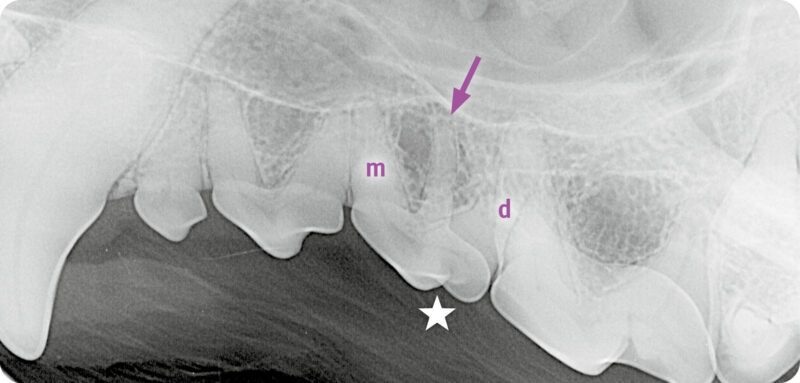

Röntgenbeispiel Hund: Dieser Röntgenbefund (Abb. 2) ergibt eine überzählige Wurzel (➡️) zwischen mesialer (m) und distaler (d) Wurzel des dritten Prämolaren (⭐️) im linken Oberkiefer. Dahingegen ist das Röntgenbild des Oberkiefers rechts unauffällig.